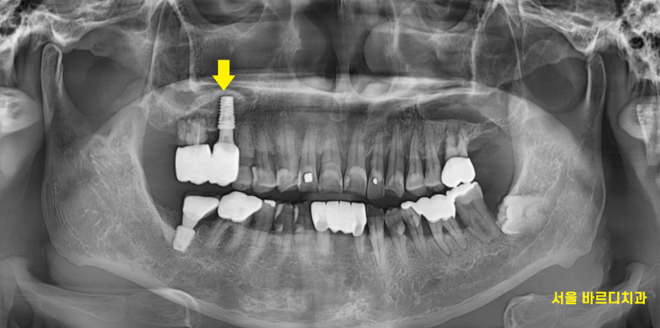

230708

우선 상황이 안좋긴 하지만

가장 불편함을 호소하신 치아 1개만 제거

임플란트를 시행하였습니다.

231118

다른 안좋은 치아들은

관리하면서 최대한 잇몸 무너지는 것을 방지하기로 계획해드렸습니다.

강일동 임플란트가 완성되기까지

다른 부위 잇몸치료도 진행해드리고

염증 치료를 시행하였습니다.

더 나빠질 것을 대비하여

3개월에 한번씩 잇몸 관리를 해드리기로 하였는데요.